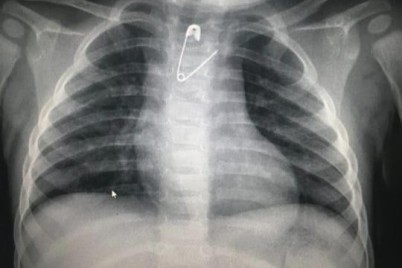

مكة المكرمة - إبراهيم البلوشي تمكَّن فريق طبي بمستشفى الولادة والأطفال عضو التجمع الصحي بمكة المكرمة من إنقاذ طفلة بعمر...